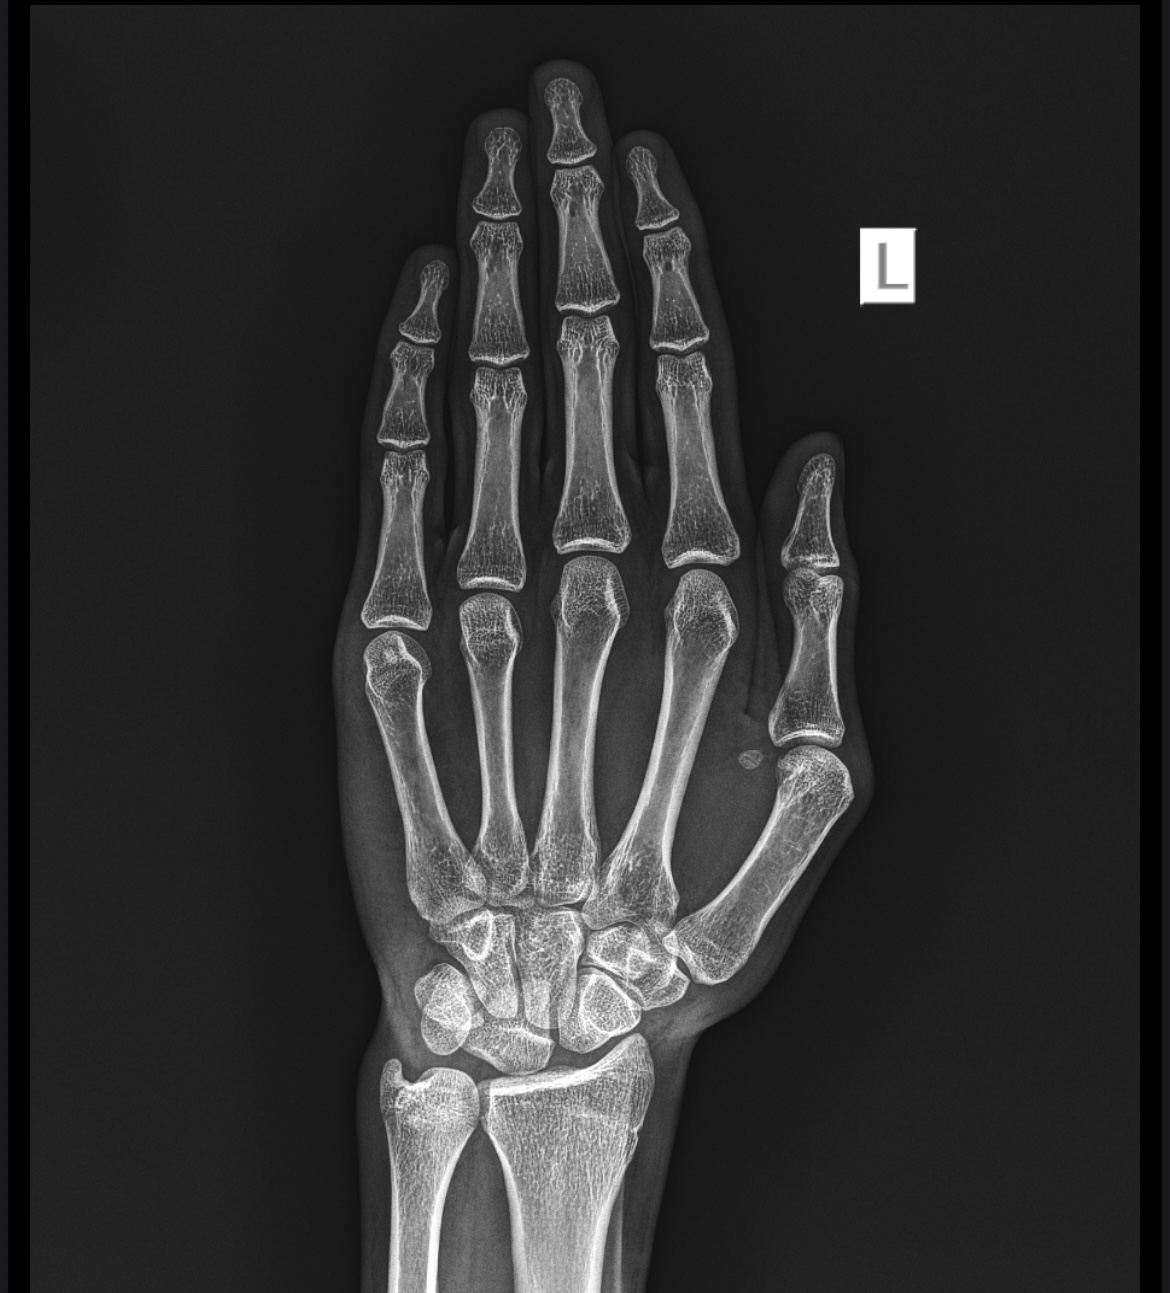

Just got my x-ray back, are my growth plates closed?

Ik it’s almost totally fused but still is there any chance I can grow a few cms?